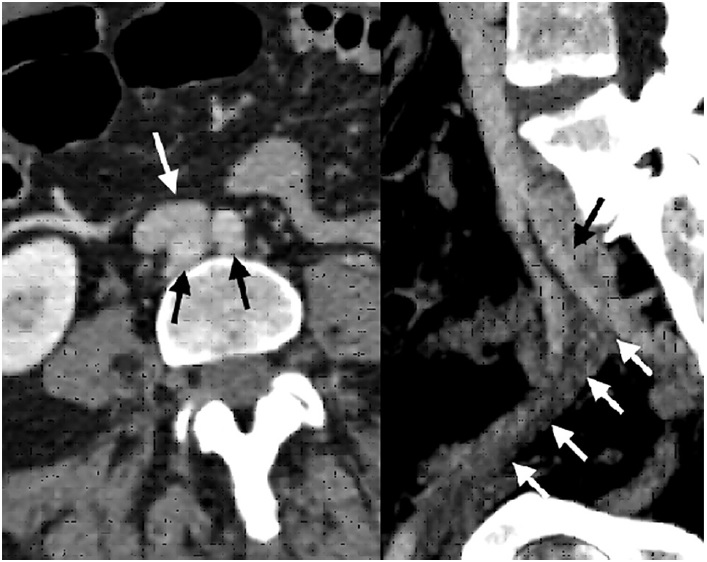

The patient underwent a computed tomography (CT) scan that reported thrombosis of the left internal jugular vein, with occlusion of the left brachiocephalic and subclavian veins (shown in Fig. 1). There was no evidence of collections/abscesses. A brief transthoracic echocardiography was performed in the ER, which rose the suspicion of thrombus/endocarditis. The subsequent transesophageal echocardiogram documented a thrombus adherent to the pacemaker leads. There was an equivocal image of vegetation. Blood cultures, blood panel with C-reactive protein (CRP) and procalcitonin (PCT) were collected. The patient was also scheduled for a repeat CT for evaluation of pulmonary embolism.

Imagen de estudio dividida en 2

Fig. 1 Left. Computed tomography angiography axial section evidencing aortic bifurcation (black arrows), behind the iliocaval junction (white arrow). Right. Sagittal section shows compression by the left hypogastric artery (black arrow) causing external iliac vein thrombosis (white arrows).

Fig. 2 Left. Initial phlebography showing thrombosis from the proximal femoral vein (white arrow), which rechannels with low flow at the common iliac vein level (black arrow). Right. Final phlebography after stent placement showing absolute permeability of the iliac axis